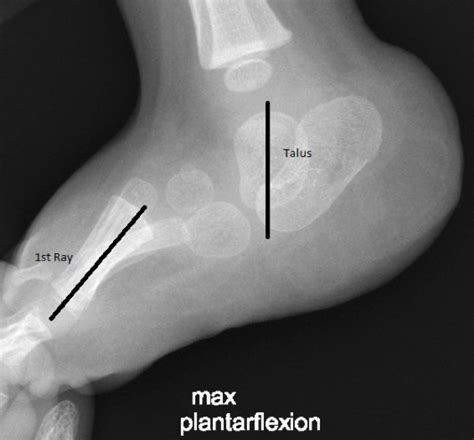

The term Rocker Bottom Feet, or congenital vertical talus in medical terminology, refers to a foot deformity where the talus bone (the main bone in the ankle joint) is locked in a fixed position. Because the bone is pushed into an abnormal angle, the foot cannot flatten or bend normally. Instead of a natural arch, the middle part of the foot curves downward, touching the ground when the individual stands.

• X-ray Imaging: This is the gold standard for diagnosis. Lateral (side-view) X-rays are typically used to measure the alignment of the talus and calcaneus bones.